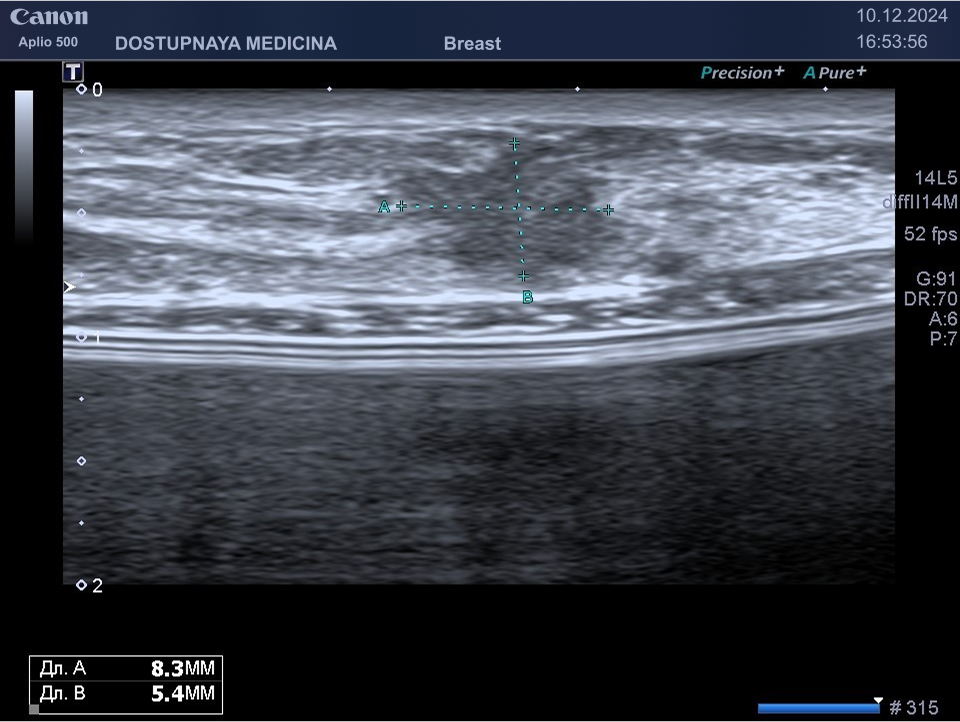

Киста молочной железы – это самое часто выявляемое образование в молочной железе во время ультразвукового исследования. Представляет собой тонкостенную полость, заполненную жидкостью.

Киста может быть заполнена жидким или густым секретом. Киста с жидким секретом на УЗИ выглядит как анэхогенное (чёрное) образование округлой или овальной формы, киста с густым секретом на УЗИ выглядит как гипоэхогенное (серое) образование.